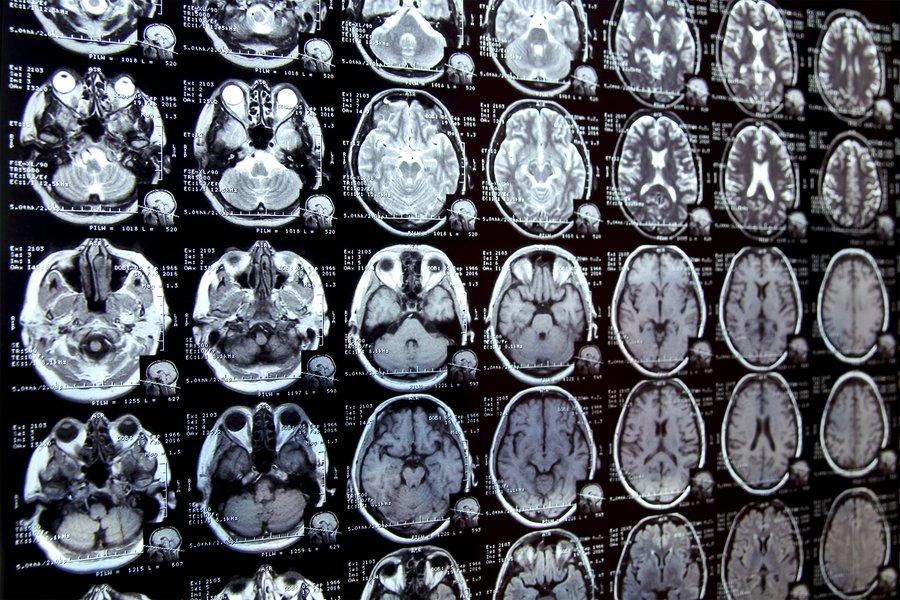

对医学图像中感兴趣区域进行标注(称为分割)通常是临床研究人员在开展涉及生物医学图像的新研究时采取的首要步骤之一。

例如,为了确定大脑海马体的大小如何随患者年龄增长而变化,科学家首先需要在一系列脑部扫描图像中勾勒出每个海马体的轮廓。对于许多结构和图像类型而言,这通常是一个手动过程,可能非常耗时,尤其是在研究区域难以界定的情况下。

为了简化流程,麻省理工学院的研究人员开发了一种基于人工智能的系统,该系统使研究人员能够通过在图像上点击、涂鸦和绘制方框来快速分割新的生物医学成像数据集。这种新的人工智能模型利用这些交互操作来预测分割结果。